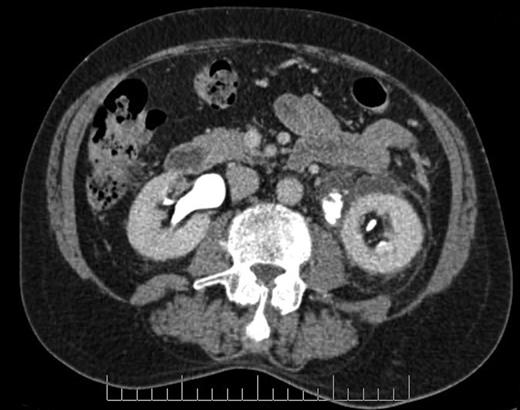

Blood tests revealed a Stage 3 acute kidney injury (baseline renal function was normal) with raised inflammatory markers and elevated PSA compared with baseline (Table 1). A mid-stream urine specimen sent for microscopy, cultures and sensitivities yielded no growth of organisms. A bedside bladder scan revealed a bladder volume of >999 ml, necessitating the insertion of a urethral catheter with a residual volume of 2.4 l, and intravenous antibiotics were commenced. An ultrasound scan (USS) of the urinary tract was performed to evaluate for the presence of hydronephrosis; but while this demonstrated a minor dilatation of the left renal pelvis, it also found a shallow fluid collection around the left kidney extending into the left lateral retroperitoneum, separate from the left psoas muscle (Fig. 1). In the urinary bladder, there was an irregular 4 cm mass on the left posterolateral aspect. In view of the findings, an urgent flexible cystoscopy was performed, revealing a massive median lobe of the prostate protruding up and back into the bladder; the ureteric orifices were not visualized because of this, and the bladder mucosa was normal. The patient subsequently underwent a computed tomography (CT) urogram, which showed bilateral fullness in the pelvicalyceal systems and confirmed a 4.8 × 4.4 × 2.8 cm fluid collection adjacent to the lower pole of the left kidney as detected on the USS, with perinephric stranding. The fluid collection was demonstrated to be extravasated urine on the delayed post-contrast images arising from a defect in the left proximal ureter, and extending down the left paracolic gutter (Figs 2 and 3). The massive prostate was also demonstrable (Fig. 3).

Axial section CT image demonstrating defect in left proximal ureter from which contrast is extravasating, with perinephric fluid collection and fat stranding.